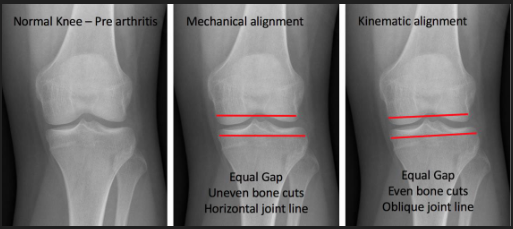

What is kinematic alignment in total knee arthroplasty?

Component placement to recreate a patient’s natural anatomy.

For varus knee for example will have varus tibial cut and vlagus femoral cut

Equivalent if not better outcomes.